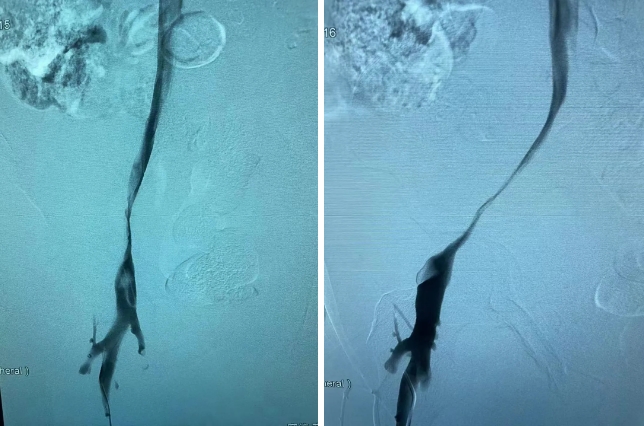

造影中證實(shí)患者右側(cè)髂靜脈重度狹窄。

右側(cè)臍靜脈重度狹窄

經(jīng)與患者及其家屬溝通后給予球囊擴(kuò)張 支架植入術(shù)。術(shù)后繼續(xù)抗凝治療,患者下肢腫脹情況完全消失,血流通暢,患者感覺(jué)良好。

球囊擴(kuò)張 支架植入術(shù)